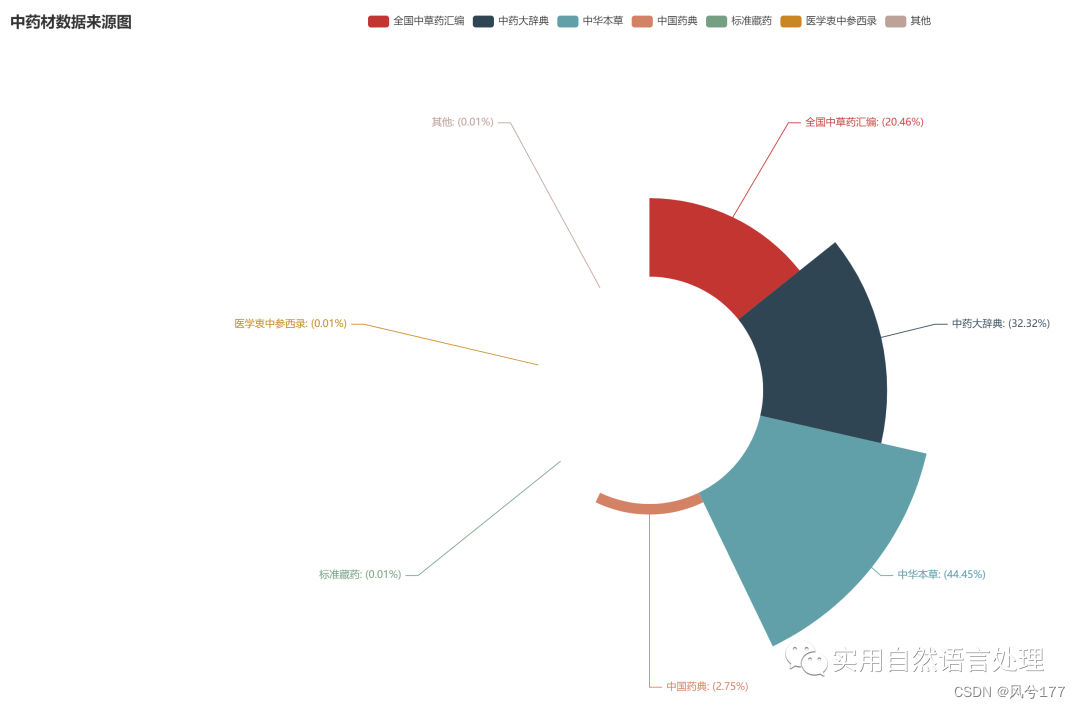

(2)中药材来源数据可视化

(3)中药材别名数据可视化